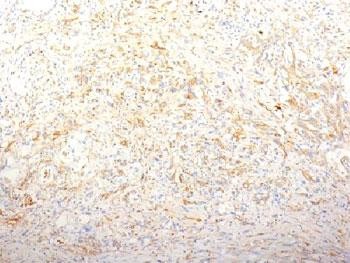

Product information "Anti-Fibronectin, clone TV-1"

1 mg/ml in sterile PBS, BSA free, sodium azide free. Fibronectin is a soluble dimeric glycoprotein of 440kDa, which is present in cells, extracellular matrix, and blood. There are two types of fibronectin: soluble fibronectin which is produced by hepatocytes and found in blood plasma, and insoluble cellular fibronectin which is produced by fibroblasts in a soluble form and latter assembled into an insoluble form via fibril formation.This antibody reacts with the cellular as well as plasma form of fibronectin. Reportedly, after iv administration, this antibody localizes to tumor vessels where it binds to the underlying basement. The Fibronectin epitope recognized by this antibody is not accessible in normal tissues to the circulating antibody indicating that it can be used to specifically target tumor vessels in vivo. Clone TV-1 fibronectin antibody is reportedly useful for delivering vasoactive agents to tumors to induce increased vascular permeability or blood flow prior to treatment with chemotherapeutic drugs or antibodies. Protein function: Fibronectins bind cell surfaces and various compounds including collagen, fibrin, heparin, DNA, and actin. Fibronectins are involved in cell adhesion, cell motility, opsonization, wound healing, and maintenance of cell shape. Involved in osteoblast compaction through the fibronectin fibrillogenesis cell-mediated matrix assembly process, essential for osteoblast mineralization. Participates in the regulation of type I collagen deposition by osteoblasts. [The UniProt Consortium]

| Application: | FC, IHC, IF |